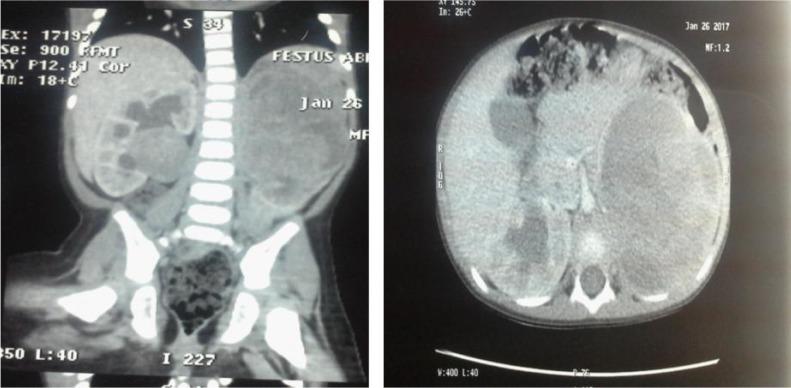

Wilms' tumour is one of the most common solid abdominal tumours in children in sub-Saharan Africa. Most cases present with an asymptomatic abdominal mass. We report a 2 year old male child who presented with acute urinary retention of 6 hours duration. He had a left flank mass and ascites, with a piece of necrotic tissue protruding from the urethral meatus. The urinary retention was relieved by manual removal of the necrotic tissue and passage of a Foley's urethral catheter. Abdominal ultrasound and computed tomographic scan revealed bilateral Wilms' tumour.The child commenced neoadjuvant chemotherapy and he has made significant improvement.

肾母细胞瘤是撒哈拉以南非洲儿童最常见的腹部实体瘤之一。大多数病例表现为无症状的腹部肿块。我们报告一名2岁男童,出现了持续6小时的急性尿潴留。他有左侧腰部肿块和腹水,尿道外口有一块坏死组织突出。通过手动清除坏死组织并插入Foley导尿管,尿潴留得以缓解。腹部超声和计算机断层扫描显示双侧肾母细胞瘤。该患儿开始接受新辅助化疗,目前已有显著改善。